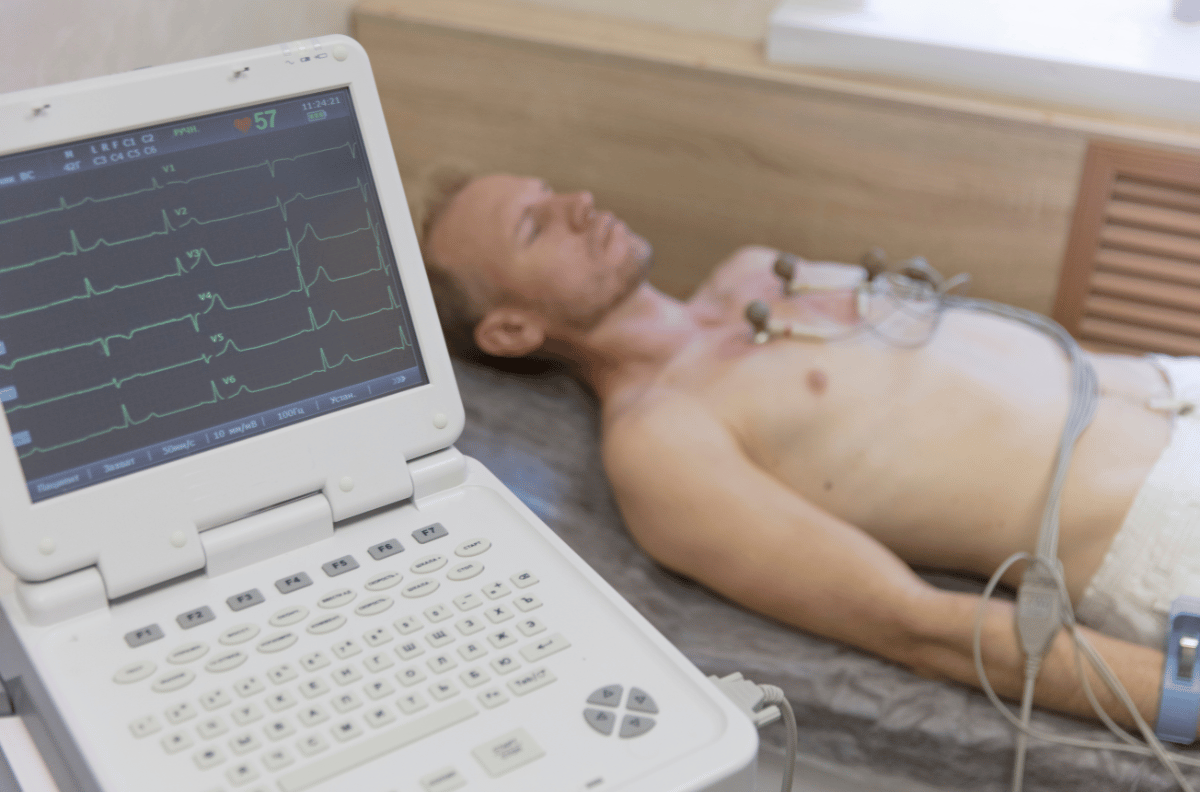

Além disso, realizamos exames laboratoriais e de imagem, incluindo exames de sangue, Doppler, eletrocardiograma, densitometria óssea, mamografia, ecocardiograma, biópsia e ultrassonografias (convencional, 3D e morfológica).

Exame que registra a atividade elétrica do coração para diagnosticar condições cardíacas.

é um exame de avaliação da atividade elétrica do coração através de eletrodos fixados na pele.